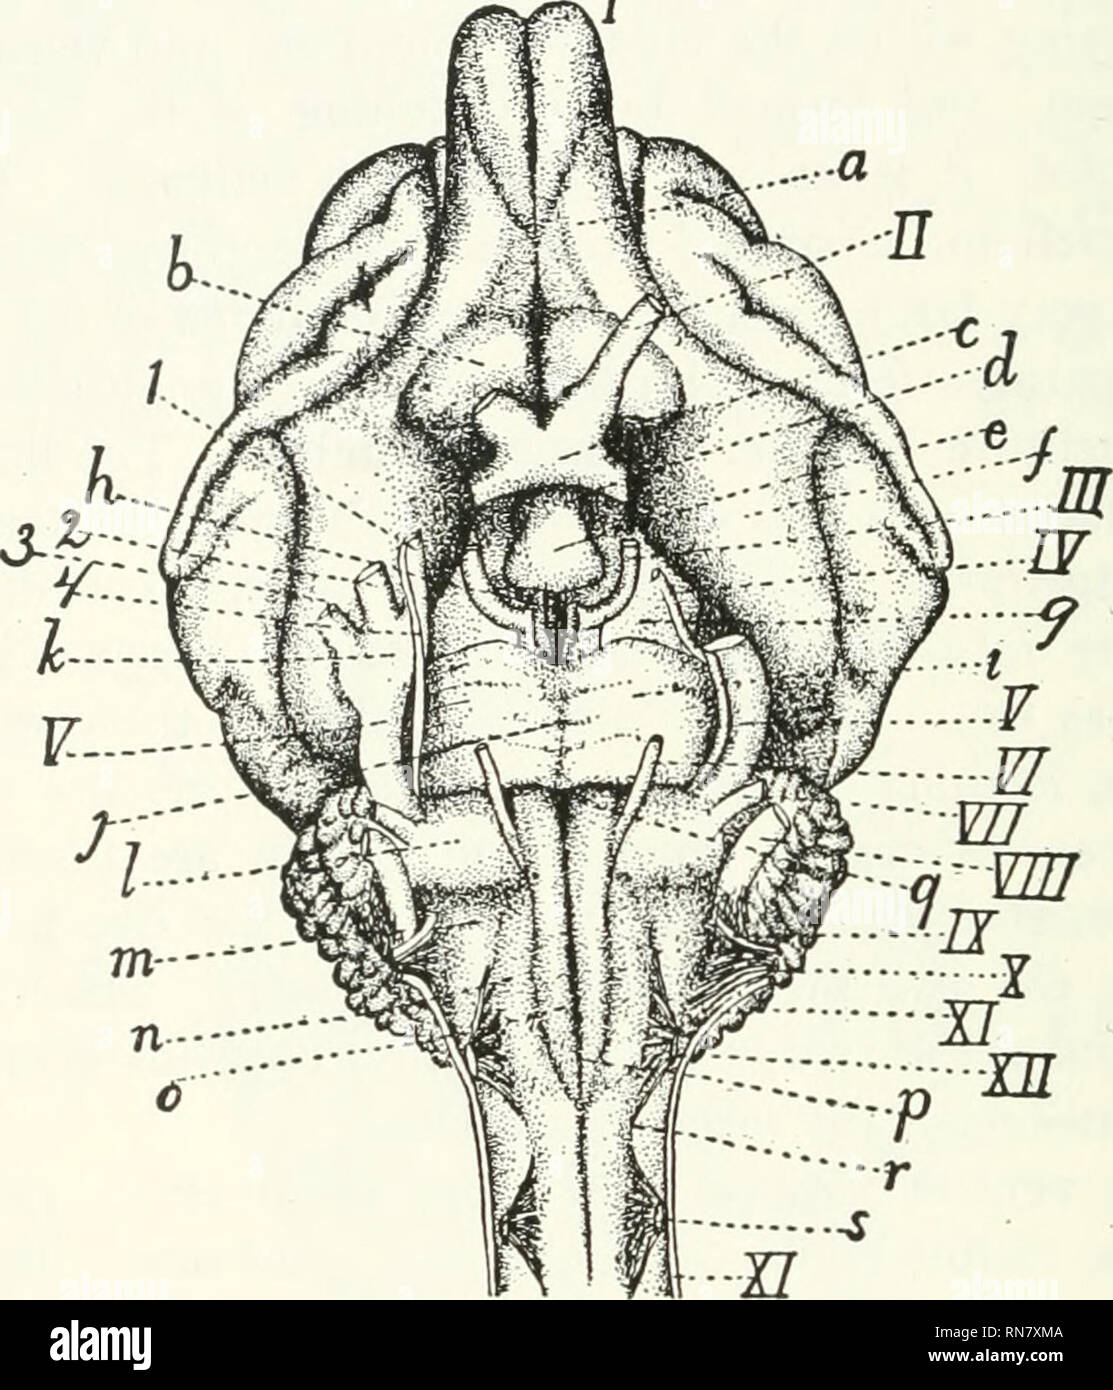

RMRN7XMA–. Anatomie der Katze. Katzen; Säugetiere. 342 NERyOUS SYSTEM. In diesem Teil des Gehirns die Fortsetzung der zentralen Hohlraum ist ein schmaler Kanal, erhält den Namen zerebrale Aquädukt (aqueductus cerebri) oder aquädukt von Sylvius. J. li Abb. 138.-ventrale Oberfläche ov das Gehirn. /-X/I, die zwölf Hirnnerven in Ordnung;/, riechkolben; //, N. opticus; ///, N. Augenmotorischen;/W, N. trochlearis; F, N. trigeminus (I, mandibularnerv; 2, maxillaris Nerv; 3, augenärztliche Nerv; 4, sensorische Wurzel); F/, N. abducens; 17/, N. facialis; 17//, N.; acuslicus LY, N. glossopharyngeus; X, N. vagus; EIN'/, N. acce

RMRDJK9R–. Praktische Anatomie der Kaninchen: Eine elementare Labor Lehrbuch in Säugerzellen Anatomie. Kaninchen; Anatomie, Vergleichende. Bezeichnungen für Platte> V. 1. Parietale Knochen. 2. Quer Sinus von duira matw. 3. Superior colliculus. 4. Zerebrale Aquädukt. 5. Isthmus rhombencephali. 6. Pons. 7. Nervus trigeminus. 8. Arteria basilaris. 9. Facialis. Xo. Knorpelige auditorischen Kapsel. Ii. Cochlea. 21. Longus capitis. 22. Rectus capitis anterior. 23. Mündliche Teil der Rachen. 24. Thyreohyoideus Muskel. 25. Sternohyoideus Muskel. 26. Mehr cornu Der hyoid. 27. Stylohyoideus großen Muskel. 28. Ein mehrsprachiges

RMRHWNBM–. Der bensley praktische Anatomie der Kaninchen: Eine elementare Labor text-Buch in Säugerzellen Anatomie. Kaninchen - - Anatomie. Bezeichnungen für PLATTE V1. Parietale Knochen. 2. Quer Sinus der Dura mater. 3. Superior colliculus. 4. Zerebrale Aquädukt. 5. Isthmus rhombencephali. 6. Pons. 7. Nervus trigeminus. 8. Arteria basilaris. 9. Gesichtsnerven. 10. Knorpelige auditorischen Kapsel. 11. Cochlea. 21. Longus capitis. 22. Rectus capitis anterior. 23. Mündliche Teil der Rachen. 24. Thyreohyoideus Muskel. 25. Sternohyoideus Muskel. 26. Mehr cornu Der hyoid. 27. Stylohyoideus großen Muskel. 28. Mehrsprachiges Arterie.

RM2AWGFW4–Erkrankungen des Nervensystems .. . "Ortion", die wir als mittleren Regen bezeichnen; hier auch wir. Abb. 43.-Rase der Gehirnnerven von Braix axd. Suchen Sie nach den Hauptabteilungen des Menschen, der Korpora qtiadrigemina (siehe Abb. 44und 45) oben, die Fissure des Sylvius unten und darunter die Faser, die an den oberen Stiegenkeln des Kleinhirns und des Pedunculi-Kleinhirns massiert wird (Abb. 46, 47, 48, 49). Seine Nticlei (Neuronzellen) liegt auf der gesamten Länge des Bodenbelägen des Aquädukts von Sylvius, von seinem frontalen Ursprung fast bis zu seinem kaudalen Ende;5 52 HISTOLOGIE DES ZENTRALEN NERVENSYSTEMS die Kerne des

RM2AWH0CG–Erkrankungen des Nervensystems .. . Abb. 13.-Diagramm des Gehirns, Der Pedonkel. (Nach Obersteiner.) Qa, Anterior corpora quaderigemina; AS, Aquädukt von Sylvius; FU:, pos-terior longitudinal Bundle; Tg, teg-mentum; Nt, roter Zellkern; SnS, substantia nigra soemmeringi; 1, frontalpontal Trakt; 2, Trakt des Motors. Kraniale Nerven; S, Hirngewebe, Hirngewebe, Hirngewebe, Hirngewebe, Hirngewebe, 5. 6, Bündel vom lem-niscus zum Fuß; 7, Stratum intermediimi. Die makroskopische ANATOMIE DES ZENTRALEN NERVENSYSTEMS 21 Rior Eminence im Menschen ist excleclingiy klein c

RM2CE564C–. Erkrankungen des Nervensystems . Abb. 43. – Basis der Braix axd Hirnnerven. Sucht nach ihren Hauptabteilungen im Menschen, der Korpora quadrigemina (siehe Abb. 44und 45) oben die Spalte von Sylvius unten, und darunter die Fasermasse der oberen Pedunkles des Kleinhirns und der Pedunculi cerebri (Abb. 46, 47, 48, 49). Seine Kerne (Neuronenzellen) liegen entlang der gesamten Länge des Aquädukts von Sylvius, von seinem frontalen Ursprung fast bis zu seinem kaudalen Ende;5 52 HISTOLOGIE DES ZENTRALNERVENSYSTEMS die Kerne der trochlearen Nerven liegen posteriorly dort, wo der aque-Ductus liegt

RM2CHEGP9–. Das Nervensystem: Ein elementares Handbuch der Anatomie und Physiologie des Nervensystems für den Einsatz von Studenten der Psychologie und Neurologie. Diese Nut der dritten Hirnnerven entstehen. Wo die Krura an die Ponen anschließt, liegen sie nahe beieinander, aber wenn sie vorwärts gehen, divergieren sie, so dass ein dreieckiger interpedukulärer Raum. Innere Struktur. - in einem transversem Abschnitt über die Mitte des Gehirns kann das Aquädukt von Sylvius in der Nähe der überlegenen Oberfläche (Abb. L 56, S. Graue Materie. - die wichtigen Massen der grauen Materie dieser Region vielleicht in vier Gruppen angeordnet : (1) die graue Materie surroun